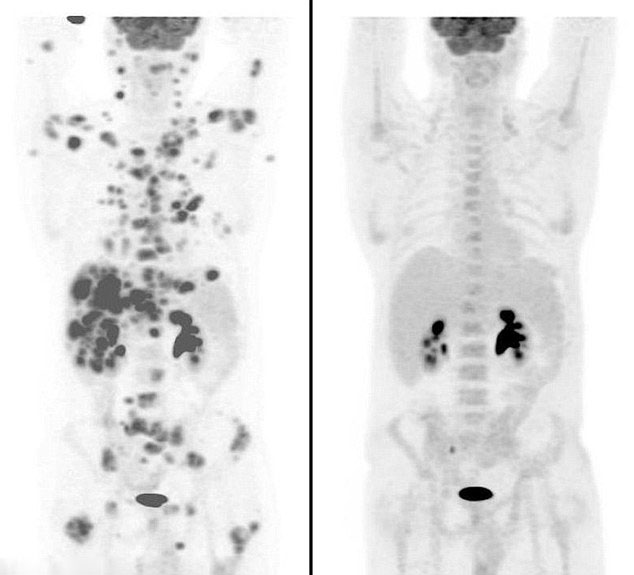

母親的日記:勵(lì)志母女抗癌記錄(組圖)

|